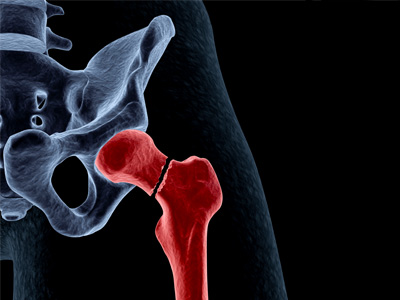

Borderline Hip Dysplasia Hip Fracture

Hip Fracture Femoral Neck Fracture

Femoral Neck Fracture Stress Fractures of the Hip

Stress Fractures of the Hip Femur Fracture

Femur Fracture Hip Instability